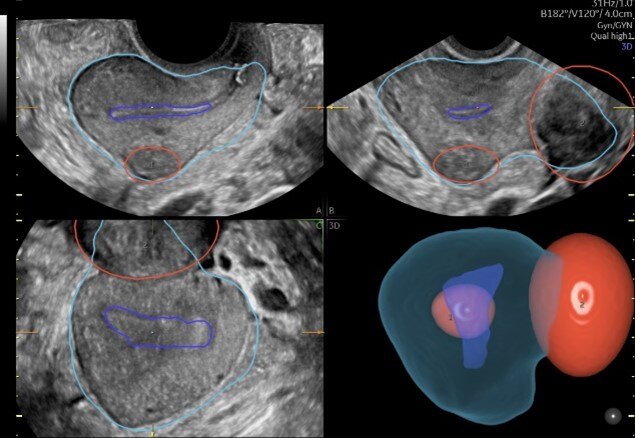

Volusonが長年培ってきた3D技術と、開発へのAI活用により、婦人科超音波検査の効率化に貢献する2つのアプリケーションを搭載。1つは、少ないステップで子宮筋腫の立体的位置関係を可視化する機能で、これまで断層像を用いて立体像をイメージしながら実施していた検査を3D画像化することで、簡便に子宮内膜との位置関係や、大きさを把握できるようサポートする(画像➀)。

(画像➀)